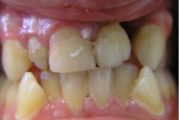

Huule-suulaelõhe ehk rahvakeeli jänesemokk on sünnidefekt, mis tekib loote arengu käigus. Tavaliselt arenevad suu ja nina välja 6. ja 12. nädala vahel. Mõnel lapsel ei kasva aga osa huulest ja suulaest kokku. Kuna huuled ja suulagi arenevad erinevalt, võib lapsel olla lõhenenud huul, Loe edasi »